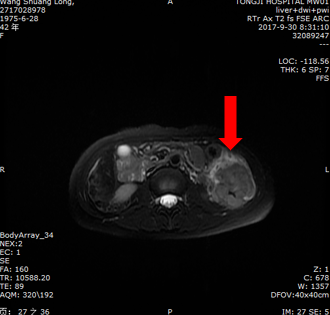

影像学检查:

腹部增强CT示:结肠脾曲及近段降结肠管壁明显增厚,考虑恶性肿瘤性病变(T4N2);双侧附件区多发囊性灶,转移性病灶可能;盆腔积液。

肝脏磁共振平扫+灌注+弥散示:结肠脾曲及降结肠占位,多为肿瘤性病变。

2017.9.26腹部CT